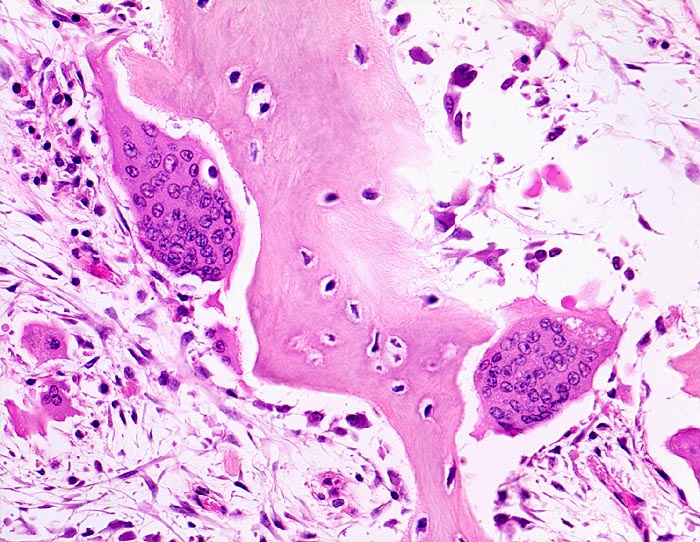

Morbus Paget des Knochens: Osteoklasten

Pathologisch gesteigerter Knochenumbau: Riesenosteoklasten mit sehr zahlreichen Kernen bauen das Knochengewebe ab. Gleichzeitig finden sich auch vermehrte kubische aktive Osteoblasten, welche Knochen anbauen. Das Mark zeigt eine lockere Fibrose.

Die Patientin hatte wiederholt über Knieschmerzen geklagt. Autoptisch zeigte das Kniegelenk eine leichte Arthrose. Aus der auffallend verdickten Tibia wurde eine Gewebsprobe zur Untersuchung entnommen.